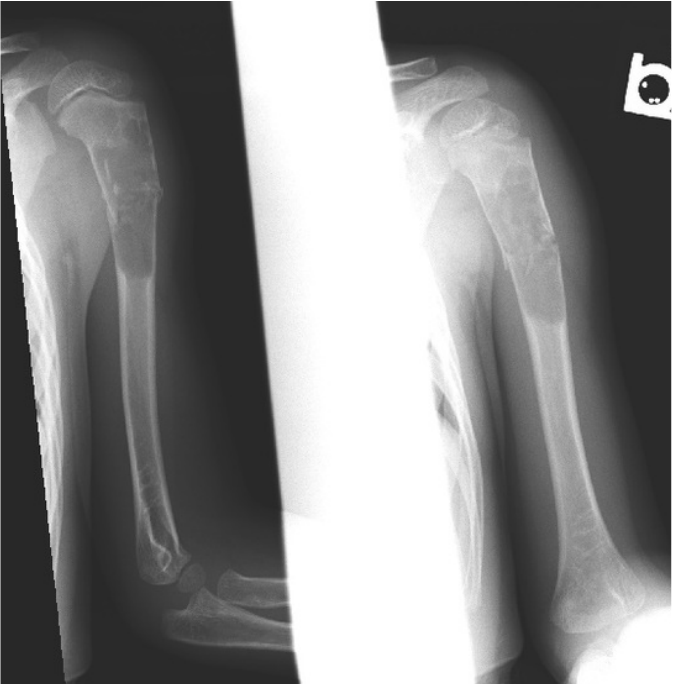

5 year old male, arm pain post fall

1.  What is the differential diagnosis?

2.  What is the diagnosis?

3.  What is the treatment plan?

Click here for September 2016 case discussion